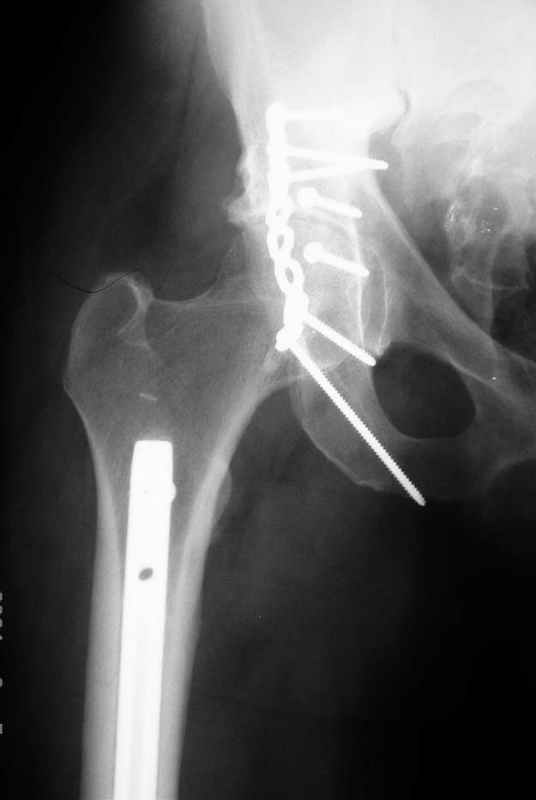

К сожалению, набора для ретроградного или антеградного реконструктивного штифтования в операционной нет, поэтому доставка заняла н-ное время. Вопрос, который возник у меня- по поводу оптимальной тактики хирургии: вся фиксация в один этап из расширенного доступа или последовательно сначала бедро и позже реконструкция впадины, комбинированный доступ к впадине отдельно к передней и задней колоннам или из расширенного илеофеморального одного доступа. Все-таки решил остановиться на одноэтапном подходе и спустя 5 дней (как раз и наборы привезли) из расширенного илеофеморального доступа сначала фиксировал реконструктивным штифтом Smith&Nephews бедро и

шейку (благо перелом шейки 2 типа -относительно стабильный) затем фрагмент крыла подвздошной кости Lag screw, далее пластина на заднюю колонну и винты в переднюю колонну.(с размерами и направлением винтов ошибка вышла:-((, но интраоперационно у меня была полная уверенность , что винты *ушли* в лонную кость).

Еще раз спасибо за комментарии и готовность помочь с имплантами. Постоп картинки в приложении,